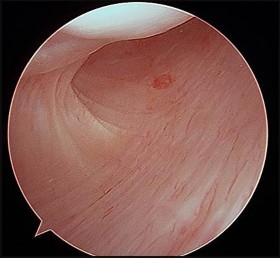

Which image seen during arthroscopic treatment is most likely associated with this patient’s condition?

An otherwise healthy 31-year-old man has had right knee pain for the past 9 months. His former physician

administered a cortisone injection and ordered 6 months of physical therapy. The patient later had an arthroscopy with debridement of the right knee by another physician and completed another course of physical therapy. The patient received minimal relief from these treatments and still is not able to walk longer distances or go on hikes. On examination, he is a healthy appearing male with a body mass index of 24 kg/m2. He has a small effusion, minimal quadriceps atrophy, no tenderness about the knee, full range of motion, stable to varus and valgus stress at 30° of flexion, a grade 1 Lachman test, and a normal posterior drawer. Figures 1 through 4 are his arthroscopic views, radiograph and MRI scan from his prior surgical procedure. What is the next most appropriate step in treatment?